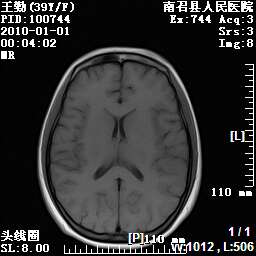

以下是引用随光逐影在2010-1-22 9:03:00的发言:[br]考虑左侧中颅窝(蝶骨翼区)脑膜瘤侵犯蝶骨翼并突入左侧眼眶。

以下是引用水过无痕在2010-1-22 14:55:00的发言:[br]一、定位:颅外占位;二、定性:恶性可能性大;三、组织来源:来源于左侧眼外直肌或其他部位;考虑为:横纹肌肉瘤>转移瘤>脑膜瘤.